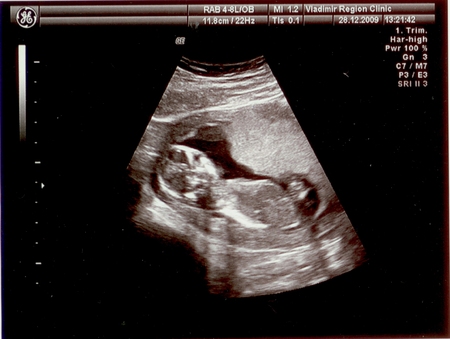

А вот мое маленькое счастье:

Записал нас муж на 12:30, в областную больницу к проф. Буланову, о котором неимоверное количество положительных отзывов. Были на месте в 12:15. Очередь. Ждали до часу. В час они ушли на обед. В 13:30 меня приняли. Ввиду большой очереди после меня УЗИ сделали очень быстро, я пыталась краем глаза разглядеть своего малыша, шевелится ли он, вдруг ручкой помашет, но врач попросил меня не вертеть головой( Я даже не успела попросить пустить папу посмотреть, как он сказал: все, одевайтесь, у вас все хорошо. отклонений нет. И это все. Хотя я слышала, что доктор очень внимательный, все рассказывает, показывает, я надеялась хотябы посмотреть на малыша на экране, послушать его сердечко, я же заплатила за УЗИ... А в итоге мне просто дали маленькую фотографию и листочек с записями: КТР 8,2 см; БПР 2,4 см;14 нед; воротниковое пространство 0,14; сердцебиение +, движения +. Знаю, что плакать нет повода, ведь главное, что с малышком все нормально, но мне так обидно, что слезы текут сами собой. Я так долго ждала этого УЗИ